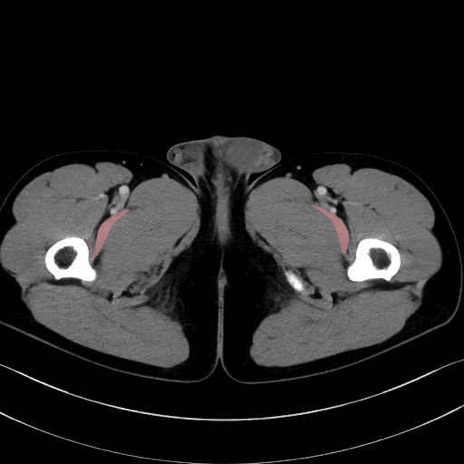

恥骨筋 (Pectineus)